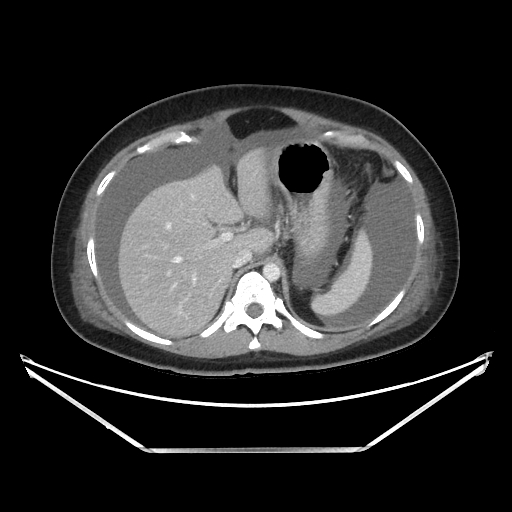

Ovarian hyperstimulation syndrome (OHSS) is a potentially life-threatening complication of assisted reproductive technology (ART). Here, we present the case report of a 30-year-old female undergoing infertility treatment who presented to the emergency department (ED) with nausea and vomiting, abdominal distention, and shortness of breath. On physical exam, she had notable ascites. Computed tomography (CT) of the abdomen and pelvis and pelvic ultrasound (US) revealed significant ascites and enlarged ovaries with multiple cysts. She was diagnosed with severe OHSS and admitted to obstetrics and gynecology (OBGYN) service for five days where she underwent intravenous (IV) hydration and paracentesis. This case report reviews the clinical presentation, categorization, management, and prevention of OHSS and provides examples of imaging findings consistent with the condition.